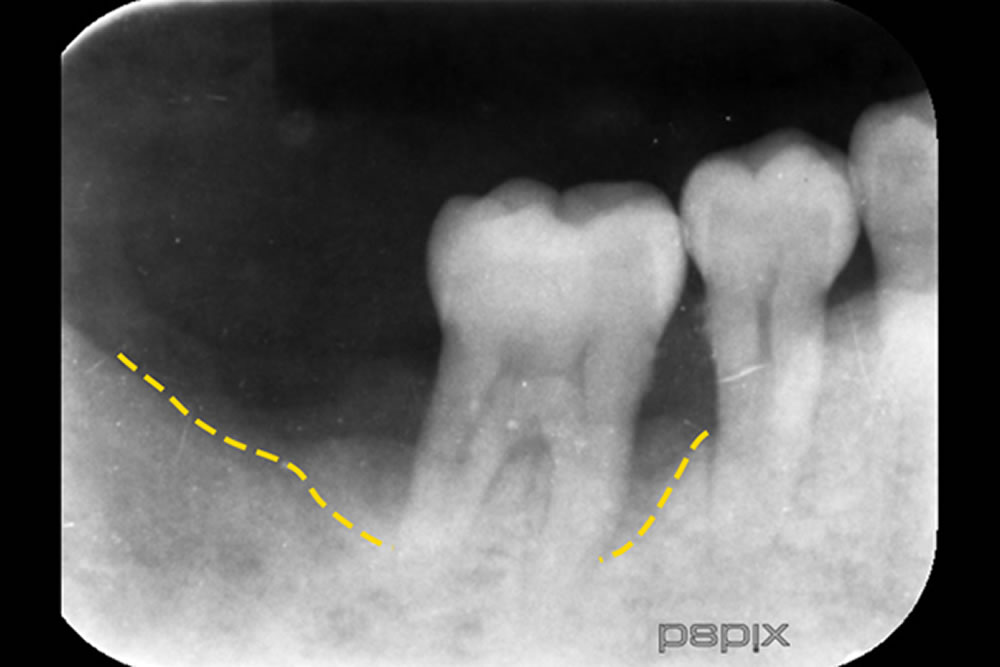

初診時(上写真)、右下6番目の歯は今にも抜け落ちそうな状態でしたが、重度歯周病治療【MINST】によって、症状を改善し、術後1年後(下写真)には歯周組織もしっかりと再生しました。

※外科処置なし・再生材料も使用しておりません。